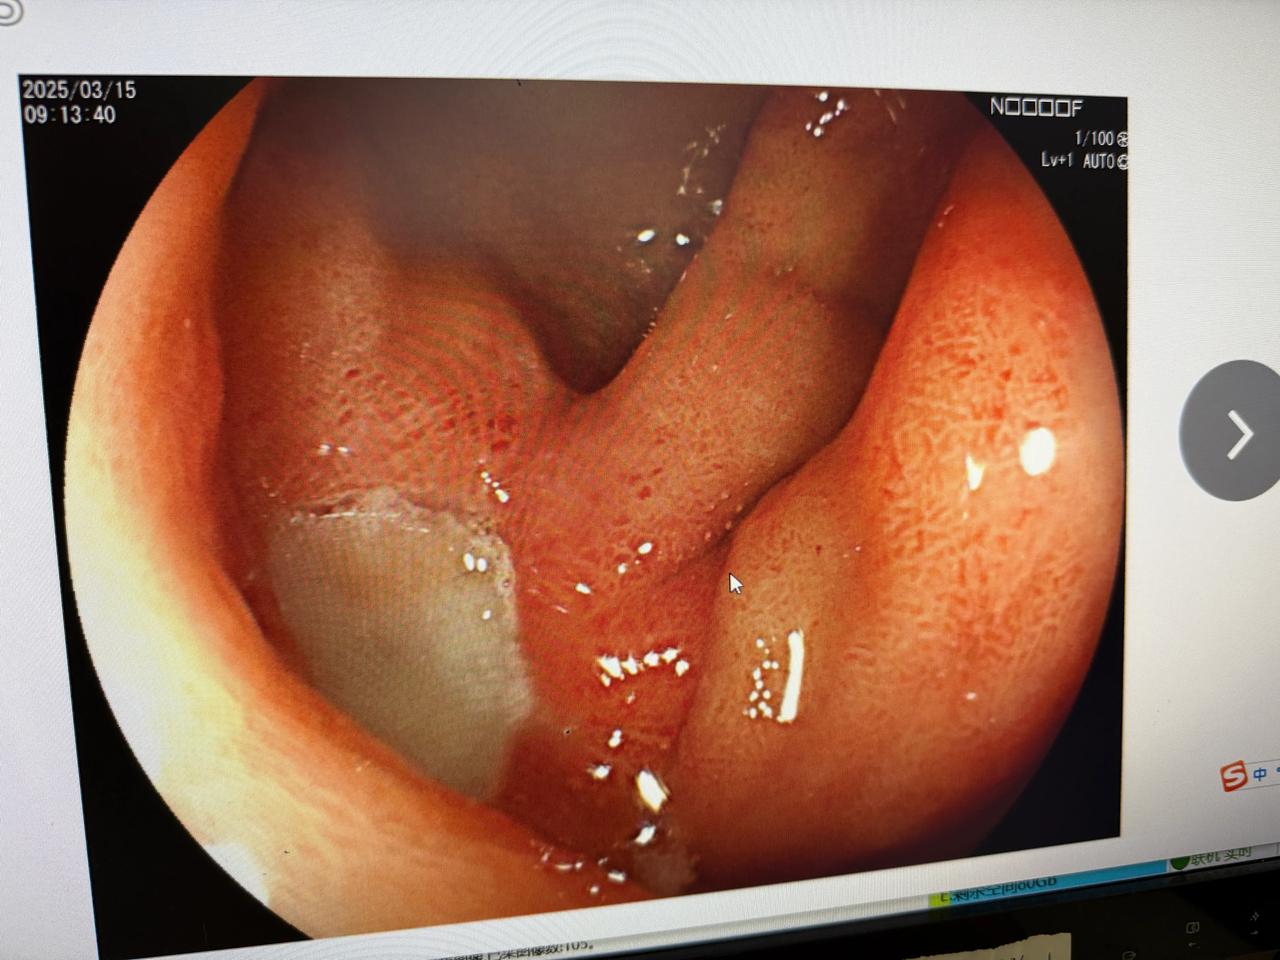

疯狂熬夜,疯狂喝酒,疯狂呕吐。 呕吐到肝肠寸断!人非常难受,周六一大早就急着来做胃镜! 胃镜下去看食管都吐撕裂开了,胃都喝出溃疡了,食道已经出现最严重的反流性食管炎了!! 做完胃镜,我在心里默念! 大哥:我啥都不服就服你! 真正的勇士不是看清生活真相后依然的爱这个世界! 而是疯狂熬夜,疯狂喝酒,疯狂呕吐。然后喝最烈的酒,最后得最严重的胃病后自然热爱这个世界!最后治疗好后依然疯狂熬夜,疯狂喝酒,疯狂呕吐。 如此往复不断循环直至尽头。 这种"自毁-治疗-再自毁"的西西弗斯式循环,本质是多巴胺阈值不断升高的成瘾表现。建议建立健康奖励机制:将省下的酒钱转化为美食或者温泉疗养基金,享受的方法有千万种不要就吊死在在酒精一棵树上! 真正的勇士不是与身体为敌,而是学会与欲望和解。 科普时间:1.反流性食管炎D级意味着食管黏膜已出现环周性溃疡,属于最严重等级。胃酸反复冲刷可使食管癌风险提升8倍,持续呕吐造成的食管撕裂更有大出血风险。 2. 十二指肠球部溃疡若深达肌层,可能引发穿孔幽门梗阻等危急情况。有数据显示酗酒者溃疡出血发生率是常人的3-5倍。 3. 酒精-呕吐循环形成恶性闭环:乙醇直接损伤胃黏膜屏障引发呕吐,胃酸二次灼伤食管疼痛影响睡眠熬夜加剧胃酸分泌。就问你怕不怕,反正我是有点害怕的